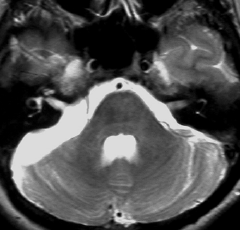

30歳くらいの時に初回の開頭手術で部分摘出を受けて,現在70代の患者さんの画像です。黄色は今も残っている腫瘍です。2度目の開頭手術,3度目の開頭手術では癒着で脳幹部や脳神経からの剥離が全くできませんでした。現在でも脳幹部に入り込むように腫瘍がゆっくり大きくなっていて,体幹失調のために車椅子生活です。顔面神経麻痺,嚥下障害,構語障害,眼球運動障害などもあります。髄液吸収障害による水頭症を併発してシャント手術も受けています。

この患者さんの40年の経過はいろいろなことを教えてくれます。似たような患者さんをたくさん見てくると,初回手術で取りきれなかった類表皮のう胞を,2度目の開頭手術で完全摘出することはとても難しいという経験を積みます。

数十年後のことを考えるのであれば,初回手術で完全摘出するべきです